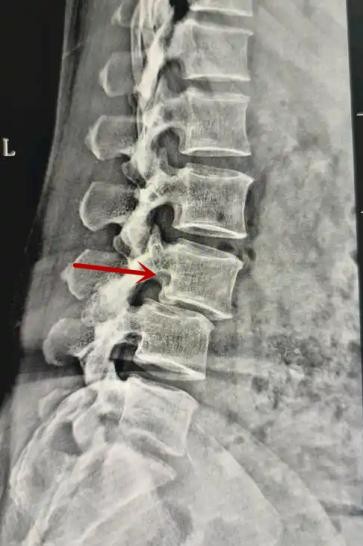

利器一:X線/DR

腰椎X線片作為最基礎(chǔ)的影像檢查手段,利于X線穿透人體組織后成像,以其快捷、直觀、價格低廉的特點,X線檢查主要包括腰椎正側(cè)位、雙斜位以及過伸過屈位。主要用于觀察腰椎骨骼的情況,如椎體是否有骨折、骨質(zhì)增生程度、生理曲度的變化、椎體移位的情況等。然而,X線檢查也有它的局限性,無法判斷是骨折的新舊,對于椎體內(nèi)部結(jié)構(gòu)和周圍肌肉韌帶組織(如脊髓神經(jīng)、椎間盤、韌帶等)的顯示不佳,另外X線作為有輻射檢查,孕婦及嬰幼兒謹(jǐn)慎選擇。

箭頭提示腰1椎骨折

箭頭提示腰3椎體滑脫